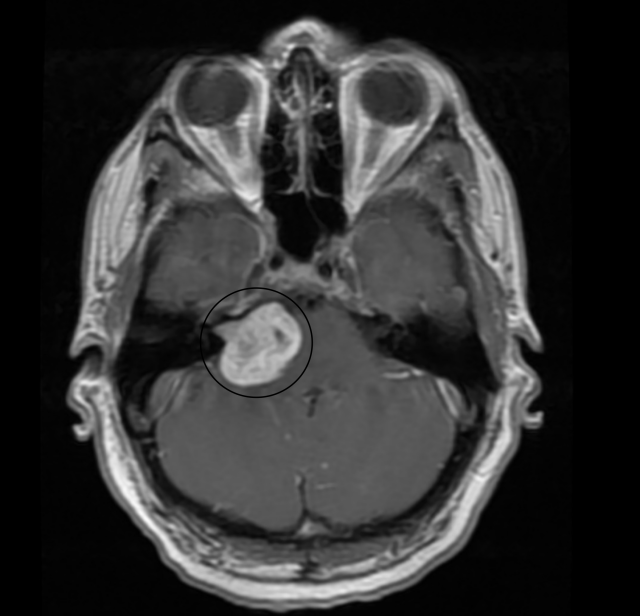

37mm Acoustic Neuroma brain tumor – pushing on my brain stem and you can see it going into my ear canal.

The MRI confirmed that this was indeed a large brain tumor and they were pretty confident it was an Acoustic Neuroma or Meningioma. I asked about operating – they weren’t sure because it was displacing my brainstem by 2-3mm and was near a large artery. I would need to go to a tertiary surgical hospital that specializes in brain surgery. It was all a bit unreal. My wife Tricia and the kids flew back that night from Florida.